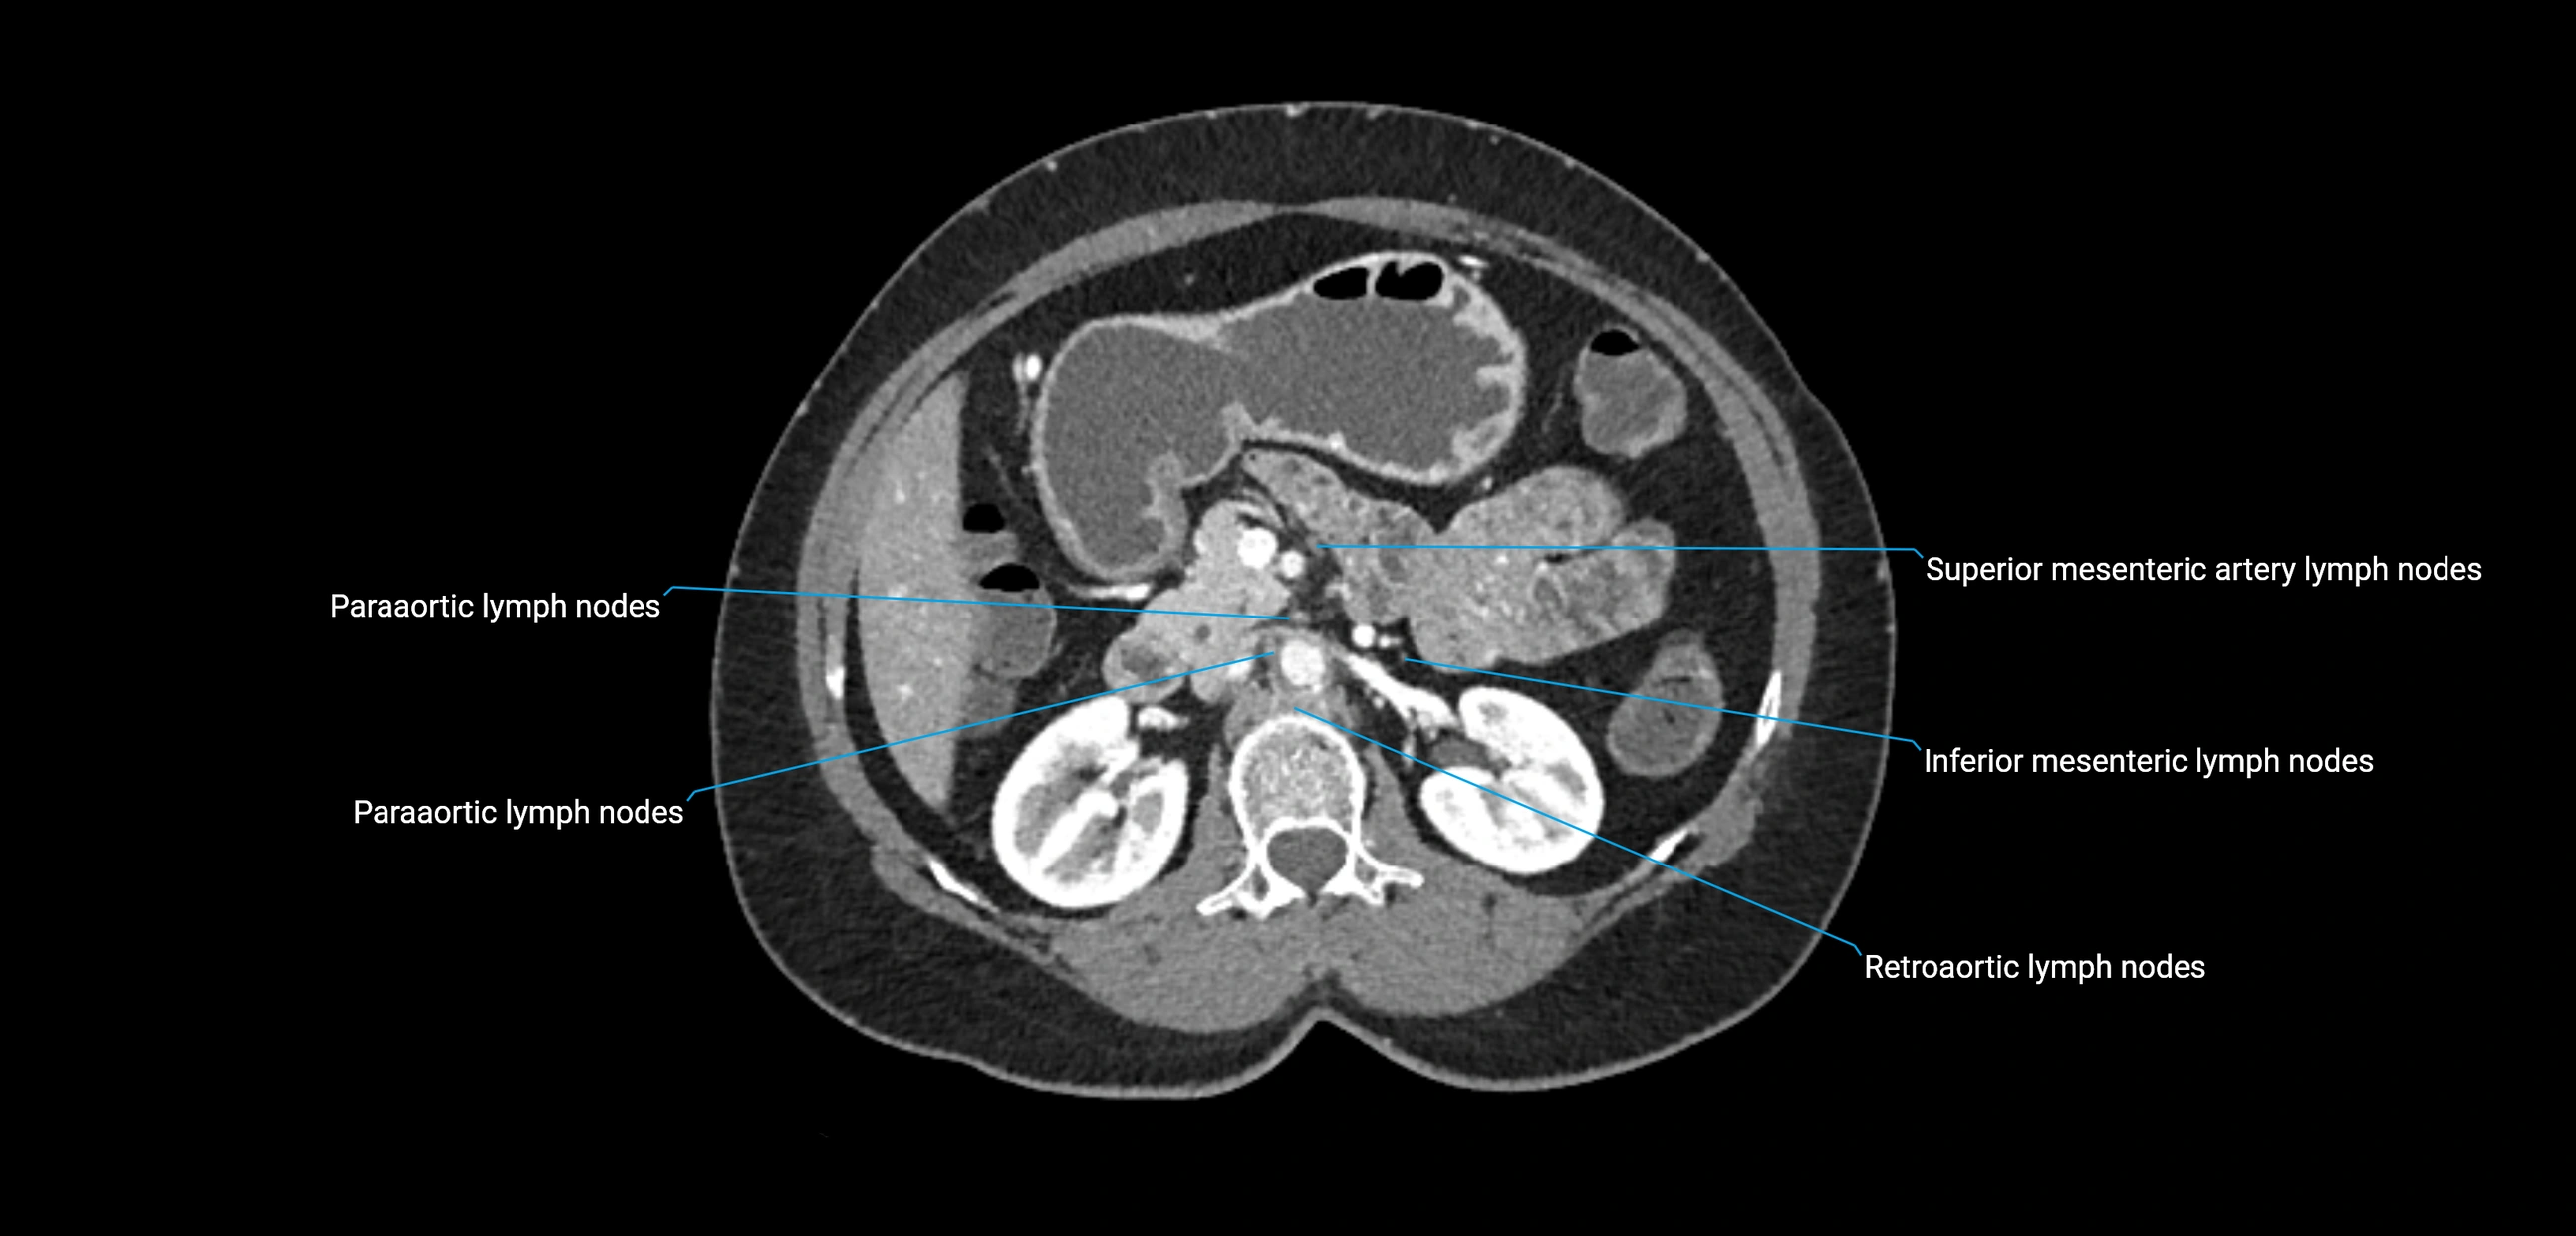

CT image

image